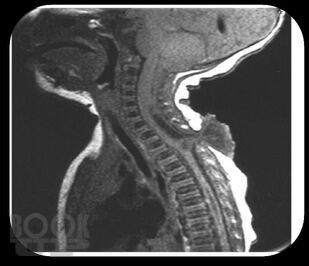

Аномалия Арнольда-Киари

В нем освещены вопросы патогенеза, современные принципы диагностики, лечебные тактики и клинические исследования пациентов с аномалией Арнольда-Киари. Пособие снабжено тестовыми заданиями и ситуационными задачами с эталонами ответов. Предназначено для обучающихся по программе ординатуры по специальности 31.08.56 Нейрохирургия.